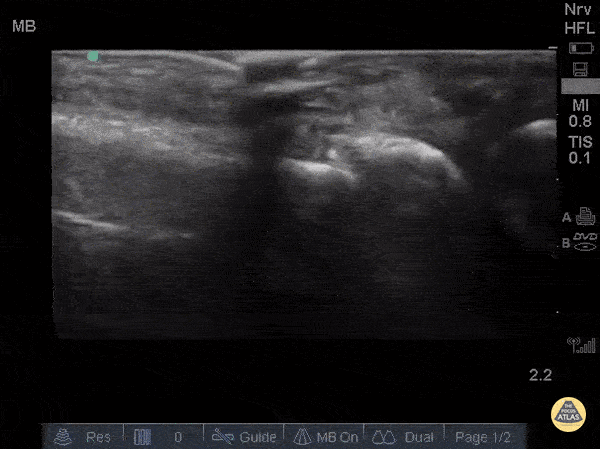

Musculoskeletal - Metacarpal Fracture

Fractures can easily be diagnosed with POCUS especially in resource limited settings. Just remember... this could be painful so use A LOT of gel and try not to press hard or at all. Gently move the probe along the axis of the bones where you suspect a fracture. The deepest and most hyperechoic horizontal line is the cortex and discontinuity in the lines represent fracture. Angulation and displacement can be measured. Two planes should be measured. Sukh Singh, MD, Caption: Matthew Riscinti, MD